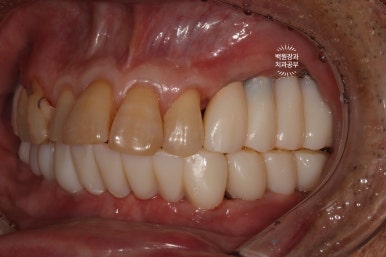

드디어 전체임플란트가 완성되었습니다!!

짜잔!!! 정말 비슷한 색상으로 제작이 잘 되어왔습니다.

최종 크라운을 연결하고나니 그렇게 깔끔할수가 없네요.

측면 사진에서도 상당히 깔끔하게 제작된 임플란트를 보실 수 있습니다!!!

최소한의 비용을 위하여 충치가 있었던 치아들은 간단히 레진으로 떼워 마무리해드렸습니다.

이렇게까지 제작해드리는데, 위턱에는 4개의 임플란트 아래턱에는 6개의 임플란트만 사용하였을 뿐입니다.

다행이라면 60대 남성분임에도 불구하고, 악궁이 작으신 편이라 12개의 치아만으로도 충분히 불편하지 않게 식사가 가능하셨습니다.